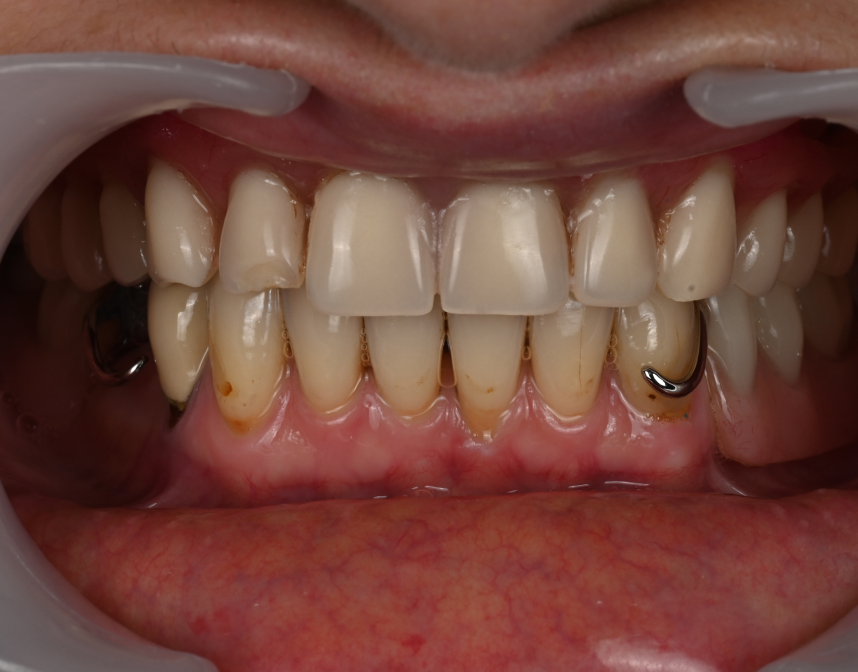

Cas cliniques

La réhabilitation globale est une solution complète pour ceux qui ont des problèmes de santé bucco-dentaire multiples et complexes. Elle consiste en un plan de traitement personnalisé, conçu pour traiter toutes les affections dentaires en une seule fois. Cette approche globale permet de restaurer l’harmonie du sourire, tout en améliorant la santé bucco-dentaire de façon durable.

Que vous souffriez de problèmes d’occlusion, de perte de dents, de maladie parodontale, ou d’autres problèmes dentaires, une réhabilitation globale pourrait être la solution pour vous. Au cabinet dentaire du Docteur Malthieu à Amiens, nous sommes fiers de pouvoir proposer cette approche intégrée à nos patients.